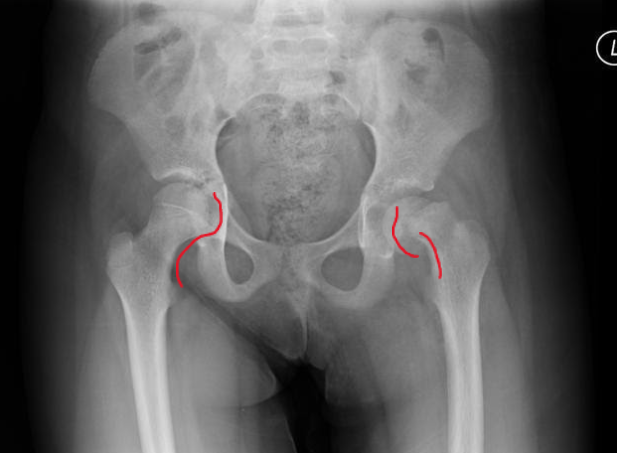

A 13-year-old obese female has had a limp for 3.5 weeks. Her x-ray is shown below.

Image 1. Case courtesy of Dr. Subhan Iqbal and Assoc Prof Frank Gaillard, Radiopaedia.org, rID: 2056